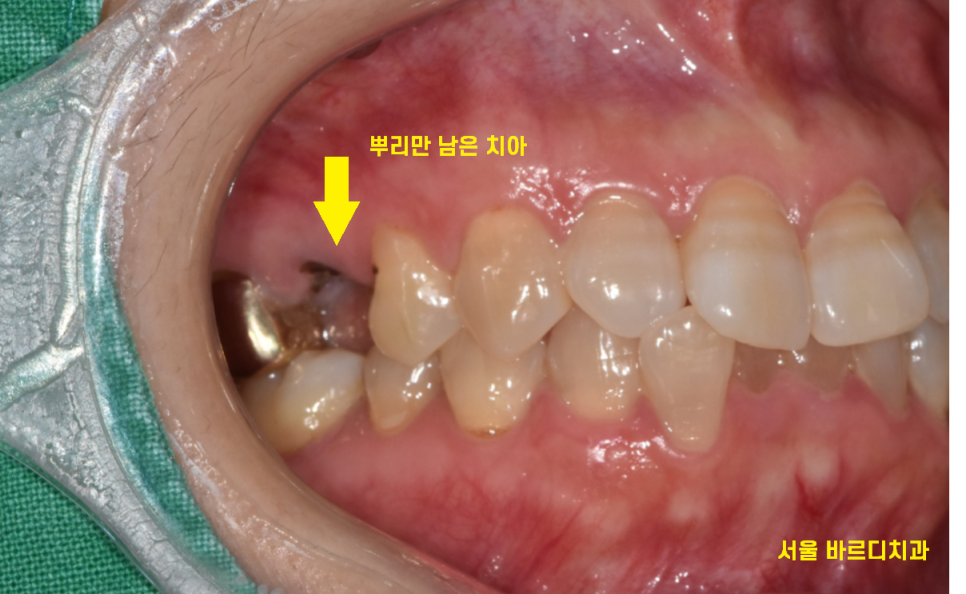

뿌리만 남은 치아입니다.

이정도로 부러졌으면 뽑고 임플란트를 해야하는데요.

뿌리만 남은 치아

뽑고 임플란트 보철까지 탈 없게

만들어 드렸습니다.